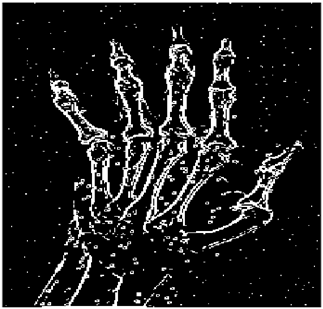

Table 5. X-ray Images.

X-ray 1X-ray 2X-ray 3X-ray 4X-ray 5

Mathematics 10 02421 i004 Mathematics 10 02421 i005 Mathematics 10 02421 i006 Mathematics 10 02421 i007 Mathematics 10 02421 i008

For the purpose of simulation, we consider two sets of images: (1) three images from MATLAB repository (Table 4) and (2) five X-ray images available online (Table 5).